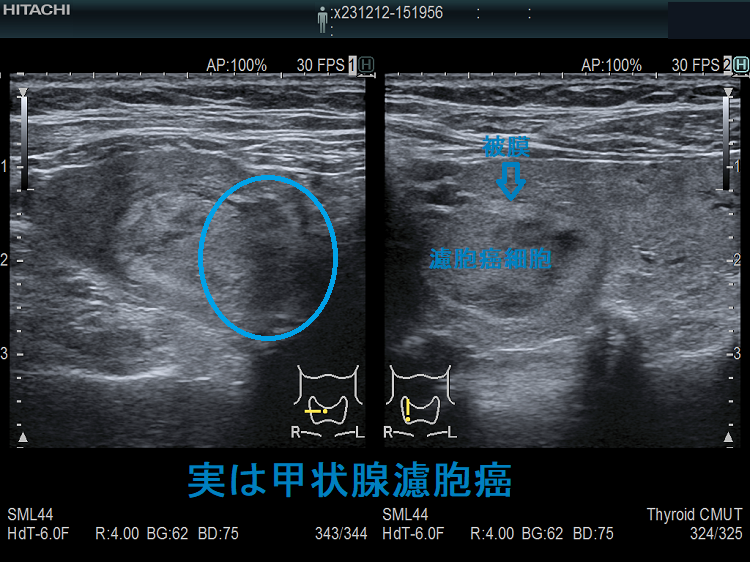

ケース① 微小浸潤型濾胞癌

穿刺細胞診しても濾胞細胞のみ、術中の迅速病理標本でも濾胞性腫瘍、摘出標本で初めて被膜浸潤が見つかり、微小浸潤型濾胞癌の確定診断が付きました。